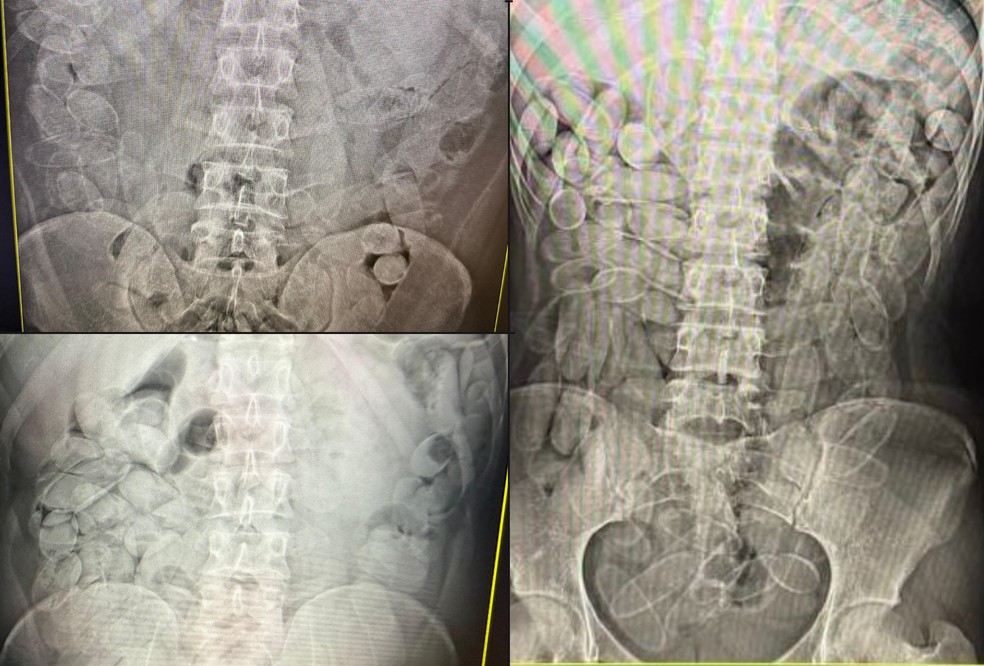

Quando há suspeita de transporte interno da droga, a pessoa é levada a uma unidade de saúde para exames de imagem. Se a presença das cápsulas for confirmada, o paciente passa a ser acompanhado por médicos até a eliminação ou retirada do material.

O método mais utilizado é a ingestão de cápsulas de cocaína. Cada pessoa ingere, em média, cerca de 100 cápsulas, o que totaliza aproximadamente 1,1 quilo de pasta base de cocaína por pessoa, conforme a auditora-fiscal da Receita Federal Tatiane Laranjo Amadeu Suhogusoff

“Eles ficam de um a três dias com a droga no organismo, até eliminarem tudo naturalmente”, informou o órgão. A escolha por esse método tem um objetivo claro: dificultar a fiscalização, segundo Tatiane.

“A droga fica dentro do corpo e não aparece em scanners de bagagem comuns. Para identificar, é necessário uso de cães farejadores e exames de raio-X, o que exige estrutura e efetivo que nem sempre estão disponíveis”, explicou a Helberth, representante da ANTT.